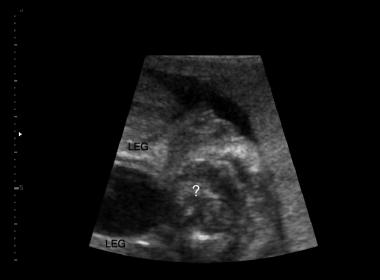

Unfortunately I have only this picture.

The gynecologist said you can see it clearly here.:think:

Please give your opinion.. Boy or Girl???